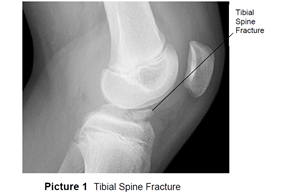

This type of force causes the ACL to pull on the tibial spine. Because the bones of children this age still have open growth plates, the ACL is stronger than the tibial spine and can pull away from the bone (avulse), causing a fracture. This is a serious injury that requires treatment with casting or surgery (Picture 1).